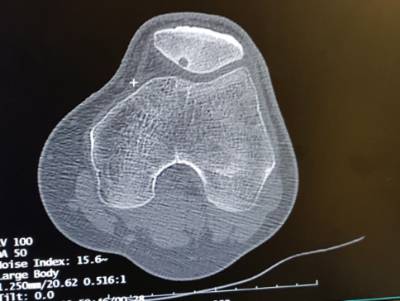

"Se trata de un osteoma osteoide al que hemos realizado una ablación. Este tipo de intervenciones no son novedosas pero, en este caso, la localización (situado en el hueso debajo del cartílago, el hueso subcondral) y su diminuto tamaño (apenas 3 milímetros) han determinado que esta intervención fuera de suma complejidad desde su origen", detalla el jefe de servicio de radiología del hospital Quirónsalud Marbella, el doctor Iván Artero.

La intervención se ha desarrollado en un periodo de tiempo limitado, apenas 2 horas y su éxito determina, además, los beneficios de un post operatorio que garantiza al paciente un proceso de recuperación notablemente más ventajoso que la cirugía convencional. "La metodología tradicional supondría fracturar la rótula, varias semanas de recuperación posterior con menores garantías de curación y una recuperación lenta, que requeriría semanas de rehabilitación. En este caso, la incisión es milimétrica y paciente recibe el alta hospitalaria apenas unas horas después de su paso por quirófano" explica el doctor Artero.

La ablación por radiofrecuencia de osteoma (ARF) está considerada una alternativa de tratamiento percutánea a la cirugía mediante aplicación de calor en el tumor, lo que provoca su necrosis. La ARF resulta muy eficaz en pacientes que no son susceptible de un tratamiento agresivo, así como para el tratamiento de tumores de forma mínimamente invasiva o que no pueden ser extirpados quirúrgicamente, siendo el tratamiento de elección en este tipo de tumores.